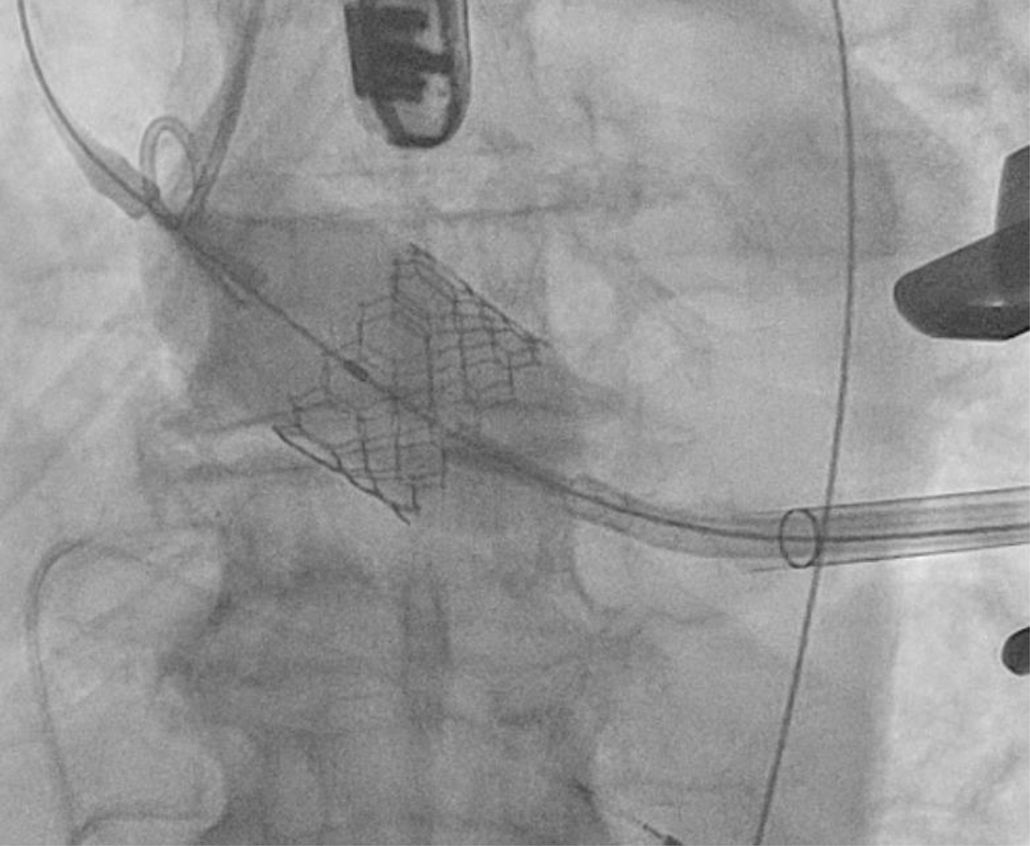

Existen numerosos escenarios que motivan el planteamiento de la post-dilatación tras el implante de una TAVI. Quizá el más importante (por su elevada frecuencia y repercusión negativa) sea la reducción de la severidad de una RPV, pues el baloneo promueve una expansión óptima de la prótesis (figs. 3 y 4). Con ello, también se consiguen un aumento del área valvular efectiva, una disminución de los gradientes y, en consecuencia, una reducción del mismatch (que se ha asociado a una mayor incidencia de trombosis valvular clínica y subclínica)46.

Li et al.49 realizaron un estudio computacional in vitro que simulaba el implante de una TAVI autoexpandible mediante dos modelos diferentes de dilatación (pre y post) con objeto de analizar su impacto en los resultados (estrés vascular, morfología del stent y RPV). Sus conclusiones argumentan que la pre-dilatación genera menor impacto que la post-dilatación, que puede mejorar la morfología protésica y, con ello, el funcionamiento y la durabilidad valvular. También optimizaría la adhesión al stent, con la subsiguiente reducción de la RPV en más del 30%.

La situación que más frecuentemente plantea la necesidad de post-dilatar es la existencia de una RPV (fig. 6). Quizá la envergadura de la misma (moderada/severa) sea uno de los factores más potentes, pero debemos atender también a otras características. Un paciente joven, de moderado/bajo riesgo, con anatomía favorable y sin comorbilidad o trastorno previo de la conducción se beneficiaría, sin duda, de la misma. También el implante de prótesis autoexpandibles, estenosis aórtica pura previa o aquellos casos en los que prima una gran durabilidad del implante.

Contrariamente, la mencionada post-dilatación puede conllevar más riesgos que beneficios en pacientes ancianos, de alto riesgo y comórbidos (trastornos de la conducción, ictus), con amenaza de rotura anular o embolización del dispositivo al añadir manipulaciones. Si durante la RPV es ligera, la anatomía hostil y en el preoperatorio presentaban doble lesión aórtica, parece también prudente obviar este paso.